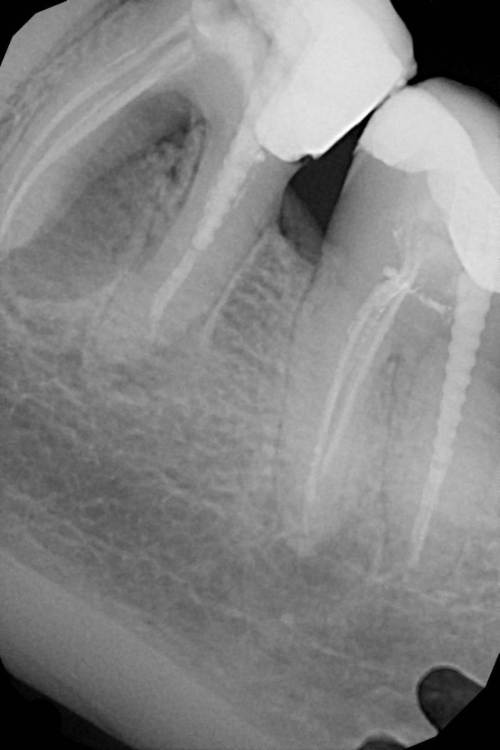

Здравствуйте. Мне 43 года. 3 Года назад перед установкой импланта пролечены были каналы 47 зуба и искуственно вывели из прикуса , чтобы небыло нагрузки , так как своей поверхности на зубе было мало. План лечения был следующий : после одномоментной имплантации  и удалению 46 зуба , сразу ставят имплант. Через 3 мес установка коронки на имплант и далее протезирование 47 зуба и введение в прикус.

Но врач ортопед  делает низкую коронку , видимо ориентируясь на 47 зуб, не беря в учет , что он не в прикусе. Переделывать отказывается , так я хожу 3 года с низкой коронкой на 46 зубе, так как мне сказали, что это норма и я должна привыкнуть , так как это искуственный зуб , и нормально , что я его не чувствую и он в прикусе. Осенью прошлого года , я все таки решила пойти к другому ортопеду , так как я так и немогла привыкнуть к этой коронке. Выяснилось , что за 3 года использования , я стерла фронт и 5 зуб и клык.  Я решила поменять коронку , но мне опять ее делают низкой . Я прошу изначально , перед слепками и объясняю ортопеду , что мне нужно выше. Но мне говорят , что врачи знают больше пациента и есть протоколы по которым действуют ортопеды , а не руководствуются ощущениями пациента.  Мне ставят коронку вновь . И вновь смыкая левую челюсть , правая у меня в воздухе. Оплачиваю , иду домой. Опять немогу жевать , жутко не удобно и мой пятый зуб задействован больше , чем 46 и 47 .

Обращаюсь к ортопедам , никто не хочет за это браться. В итоге , после моих долгих поисков нашелся человек и достал это. Я вернулась к ортопеду за коронкой. Мне опять было сказано , что сделается все как нужно , в итоге опять низкая коронка. Я попросила сделать 47 зуб коронку , в итоге она так же не в прикусе.

Высылаю фото отпечатков при прикусе , мою искривленную улыбку  панараму 2016 года до имплантации и сейчас. Так же ситуацию с 36.37

IMG_3321.JPG